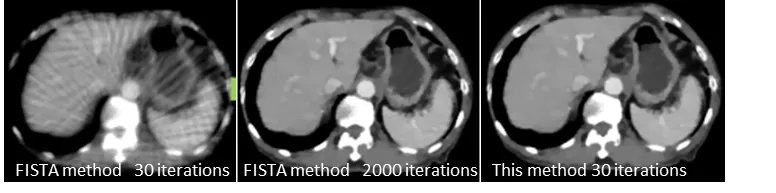

ヒトの胴体と脳に対しインテリアCT測定を行ったのち、従来方法と本技術の方法でCT画像を再構成した。その結果、従来方法ではアーティファクト(誤差)のためほとんどの情報が欠落したが(右図中央)、本技術の方法では、通常のCT画像と遜色ない高精度のインテリアCT画像が取得できた(右図右側)。この際のX線被曝量は通常のCTに比べて1/4~1/8に相当する。